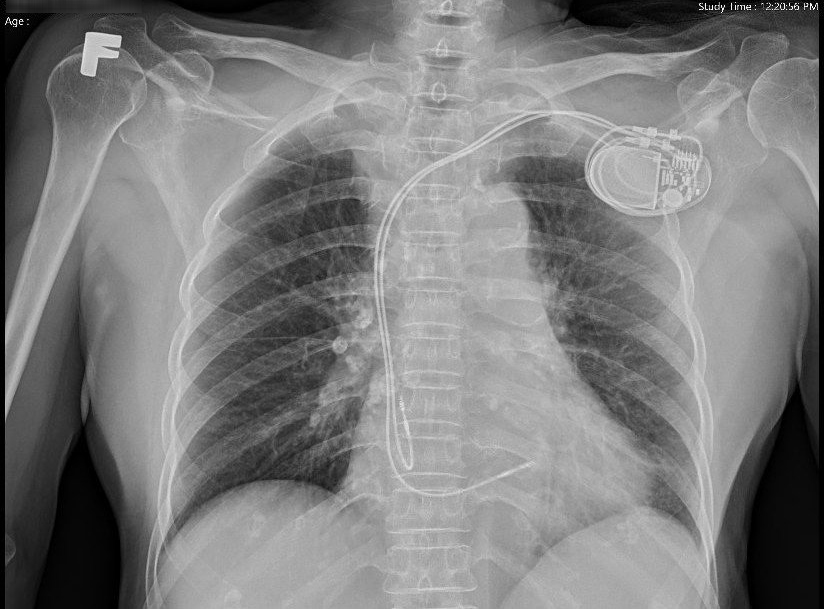

Hình ảnh X-quang ngực sau cấy máy tạo nhịp bó nhánh trái.

Hai bệnh nhân được cấp cứu đặt máy tạo nhịp tạm thời. Sau khi thăm khám kỹ lưỡng, các bác sĩ Đơn vị Rối loạn nhịp chỉ định cấy máy tạo vĩnh viễn bằng phương pháp tạo nhịp tâm thất tại vùng bó nhánh trái nhằm duy trì nhịp tim ổn định, tránh biến chứng nguy hiểm cho người bệnh. Đây là một phương pháp tạo nhịp mới trong điều trị các rối loạn nhịp chậm mang lại nhiều lợi ích cho người bệnh so với tạo nhịp truyền thống.